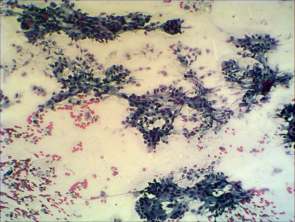

Cytological picture. There was no colloid in the background. Hyperchromatic epithelial columnar cells were found with clear cytoplasm. They were in irregular cell groups with loss of polarity and nuclear crowding.

Cytological diagnosis: a pattern corresponding to metastasis of the urinary bladder cancer.